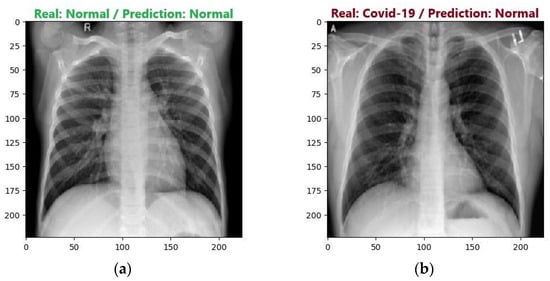

4.2.3. Analysis of Results